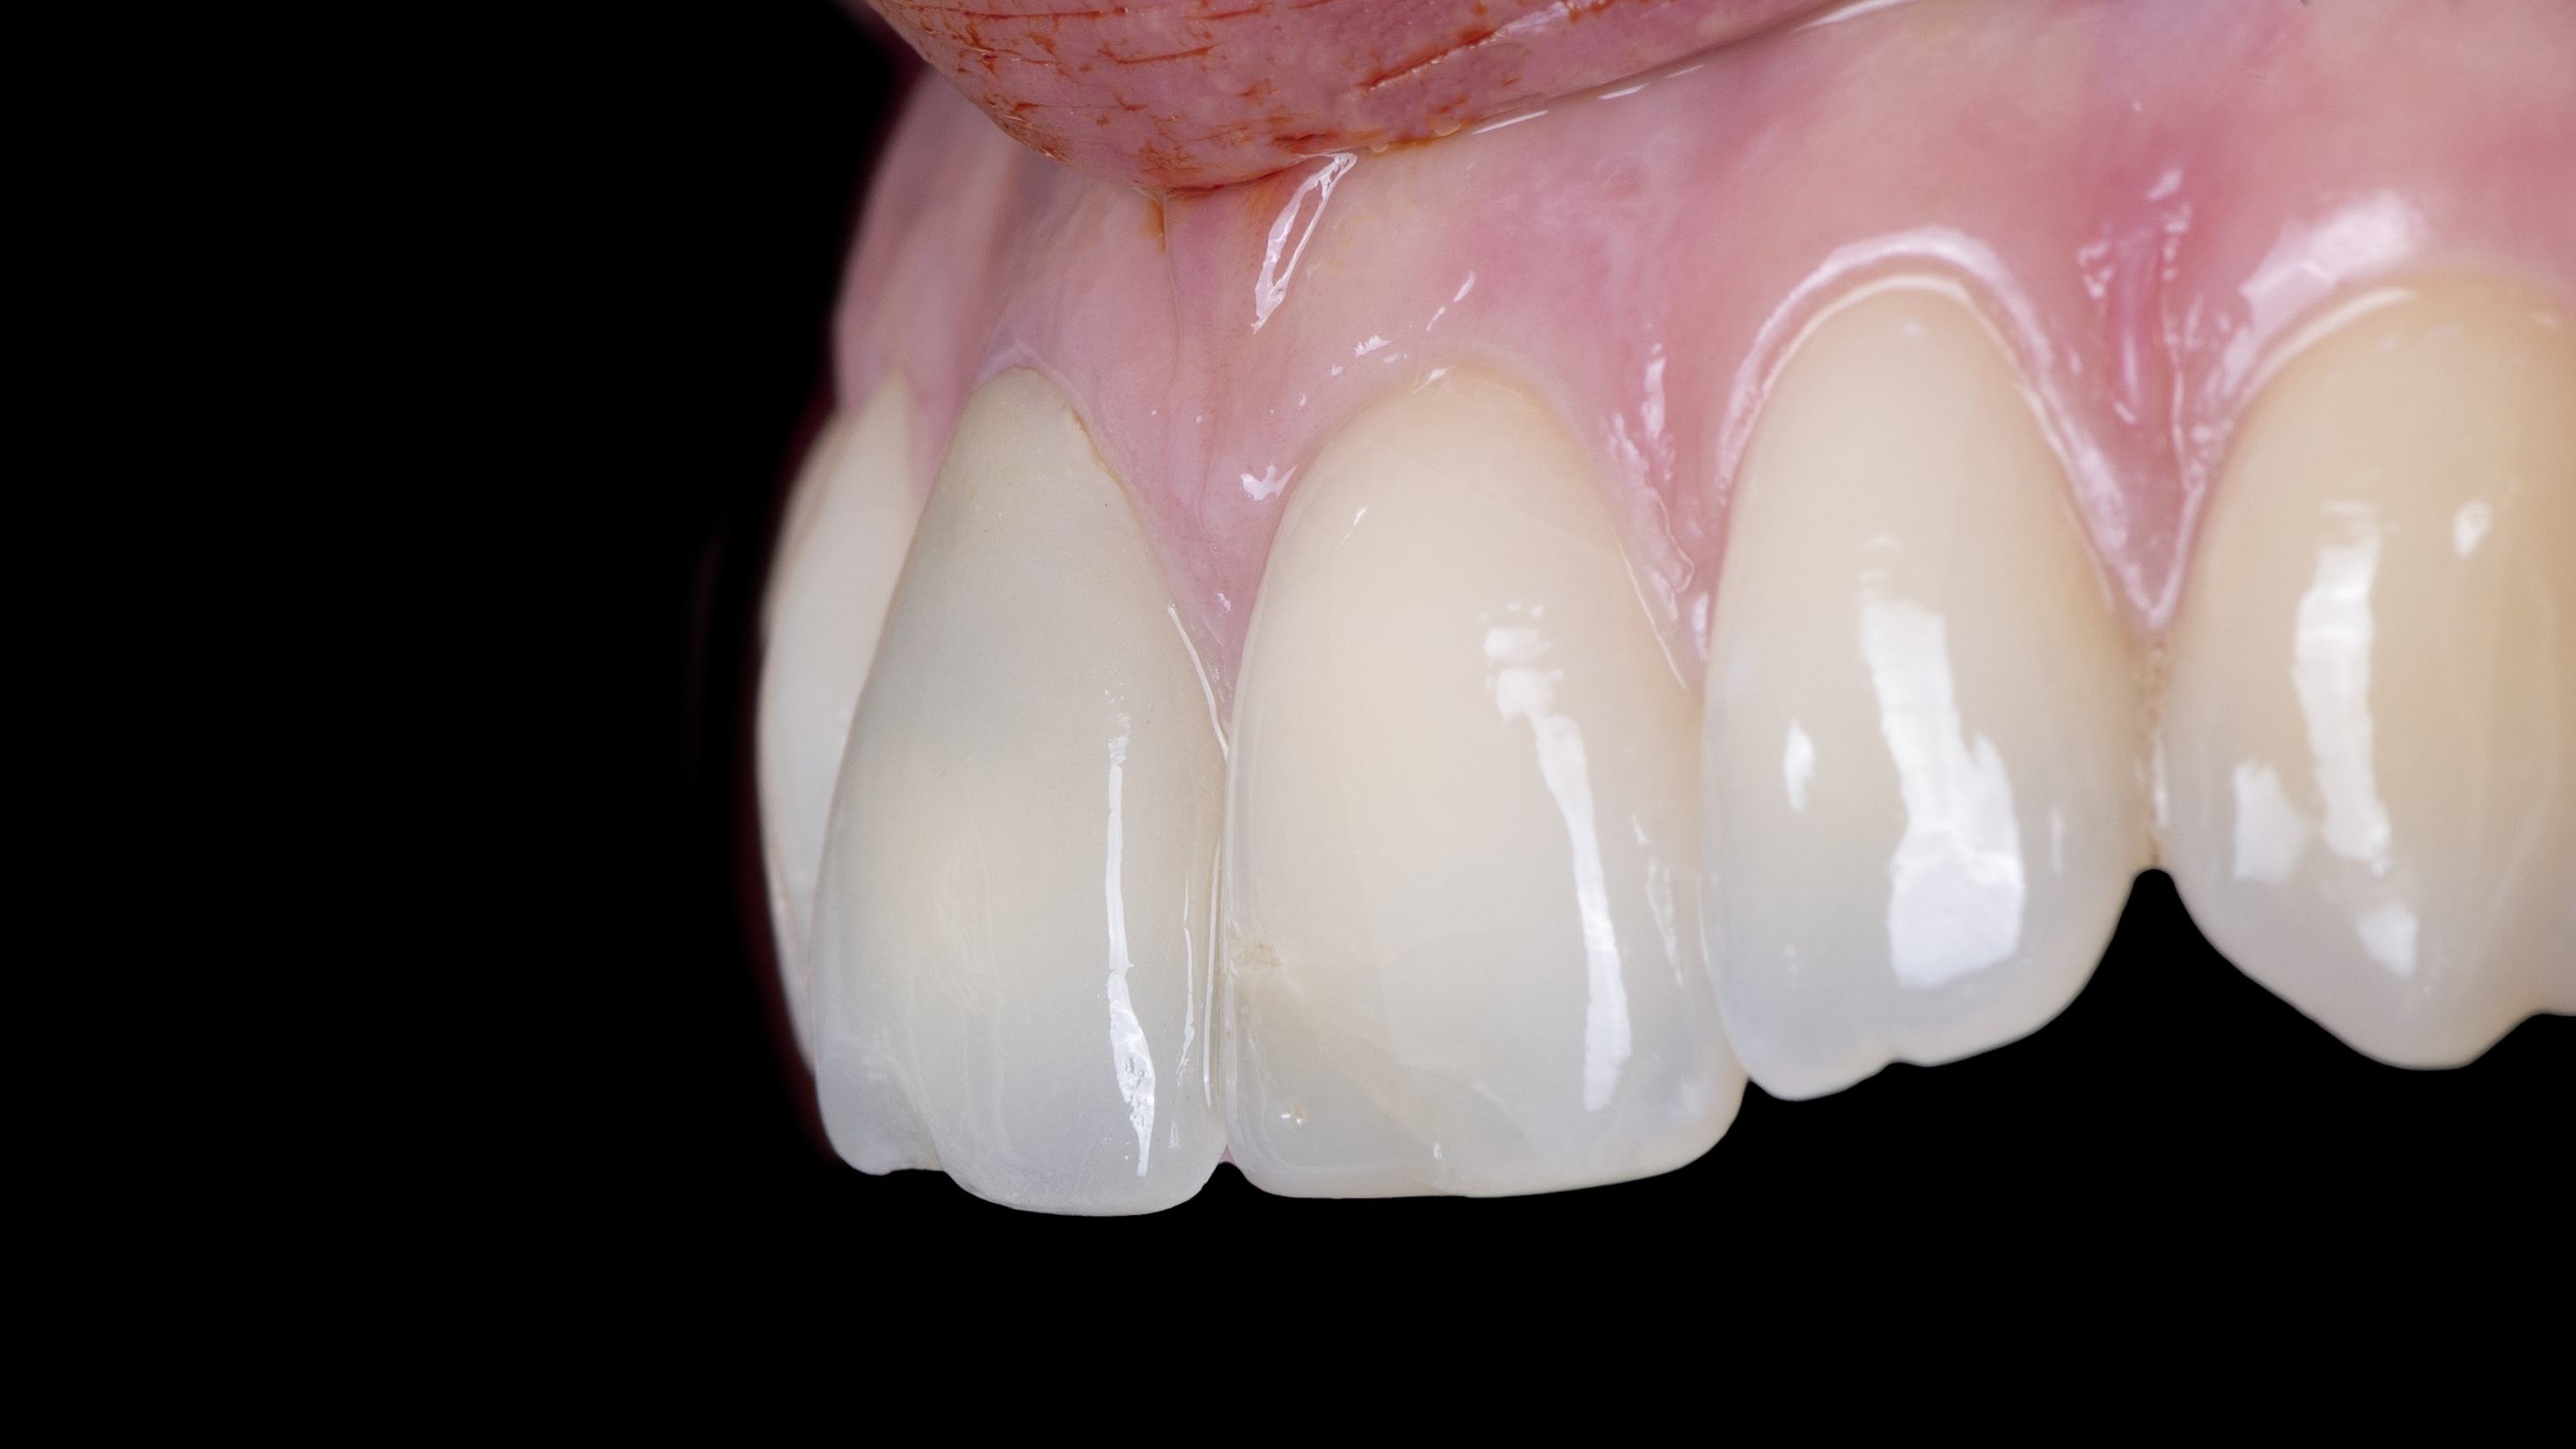

Nous constatons que la cicatrisation est alors optimale et que la prothèse d’usage s’intègre parfaitement à son environnement (Photo 20).

Intégration des réhabilitations au niveau du sourire de la patiente (Photo 26).